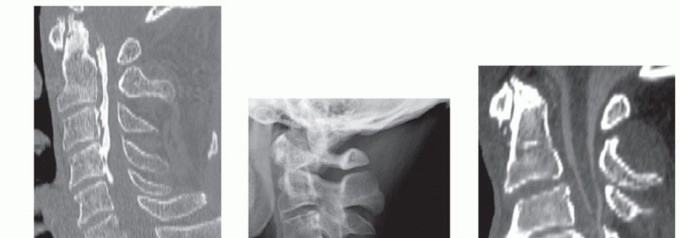

BACKGROUND Cervical spine fractures are seen in approximately 5% of trauma patients being evaluated at level …

DEFINITION Cervical myelopathy describes a constellation of signs and symptoms resulting from cervical spinal…